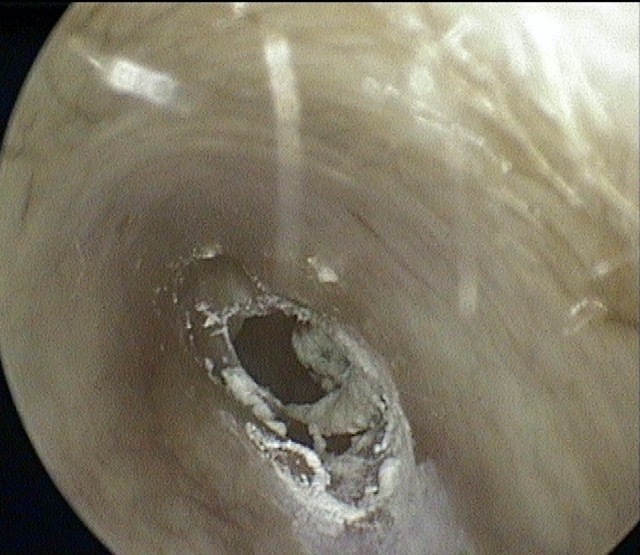

Perforation